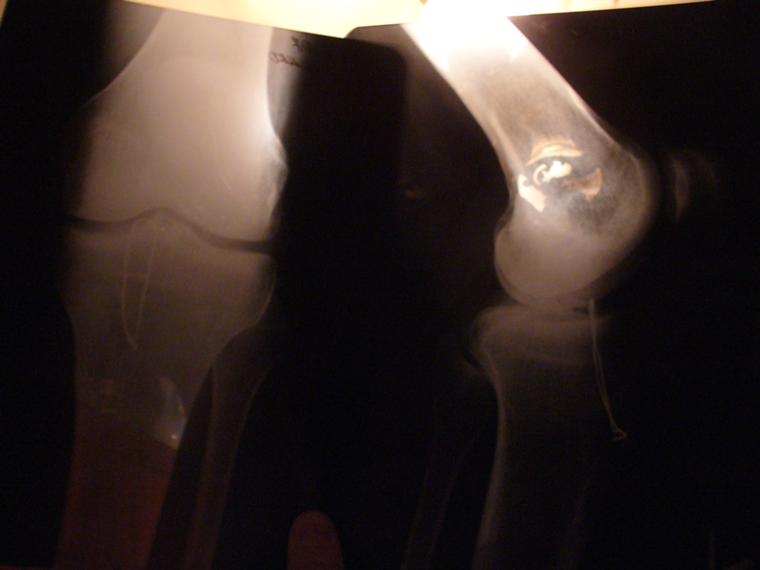

колено МАРТЫНА

полтора года назад... аццкая пролетка...сейчас дома со сломаным тазом...

а можете сказать что там на ренгене не так...?? я прост не секу в этом..

и что такова на снимке этом? булавка в коленке?

@XeL [Нояб 12, 2007 в 11:53 ]

кость внутри колена роздробленая... +порваны связки...

mega4el [Нояб 13, 2007 в 10:34 ]

уу...какая знакомая картина(( у меня было 1в1, только без связок - это жесть а не перелом